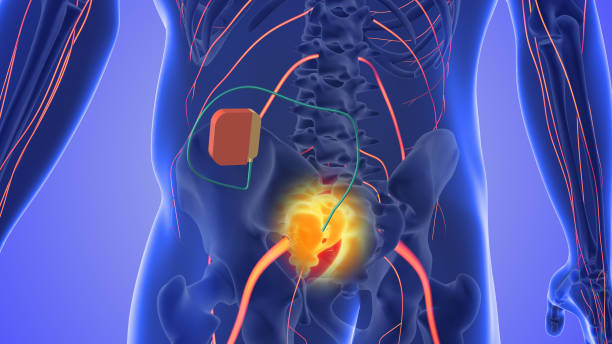

요추 전만은 허리디스크 치료와 예방에서 핵심적인 역할을 합니다. 요추 전만을 만들면 디스크의 압력이 감소하고 허리디스크 증상을 완화할 수 있습니다. 이를 위한 두 가지 자세가 있습니다.

요추 전만 자세는 디스크 환자들에게 좋을 수 있지만, 과도하게 이 자세를 유지하면 문제가 발생할 수 있습니다. 연구에 따르면 과도한 요추 전만 자세는 척추 부담과 불균형을 유발하여 디스크와 관련이 있다는 결과가 나왔습니다. 더 나아가, 과도한 요추 전만 자세가 추간판 탈출증 환자에게 골반 및 하지의 부담을 증가시킬 수도 있다는 것이 밝혀졌습니다.

요추 전만 자세를 과도하게 유지하면 디스크에 더 많은 압력이 가해질 수 있어서 오히려 척추 건강에 부정적인 영향을 미칠 수 있습니다. 그러나 대체적으로 요추 전만 자세는 디스크 환자에게 도움이 되는 자세입니다.